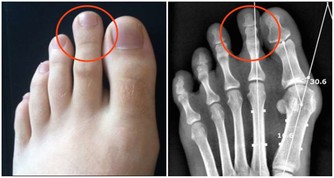

我國比較常見的慢性病有,高血壓、高脂血症、糖尿病、高尿酸血症、冠心病等,如果能夠做到將血壓、血脂、血糖、血尿酸、體重、腰圍等控制在正常範圍,可以在一定程度上減少這些疾病的發病概率。